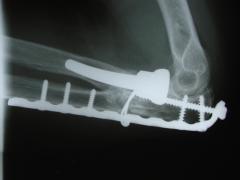

Περίπτωση 1ου ασθενούς

4 χρόνια μετά το χειρουργείο